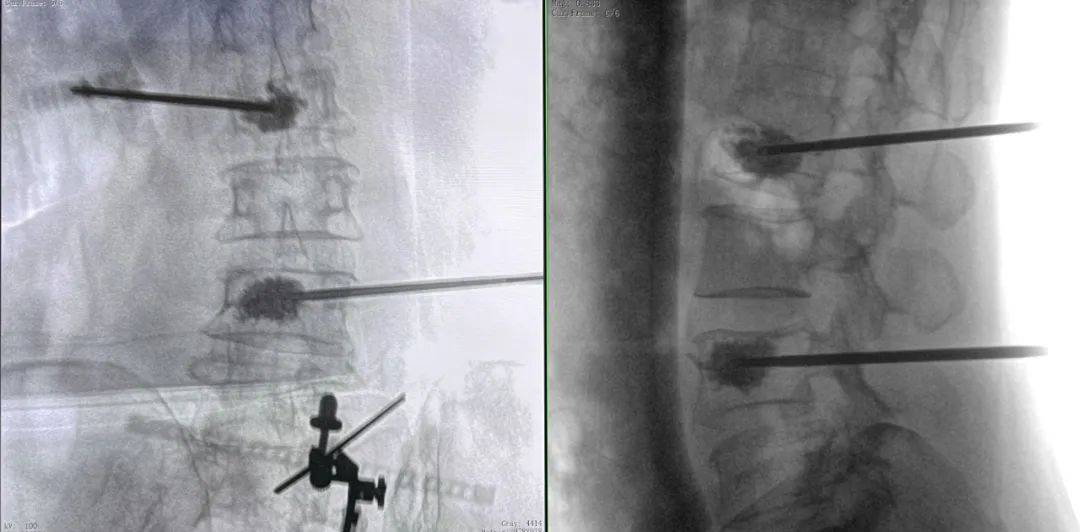

手術(shù)過程中,普愛醫(yī)療平板三維C形臂為患者拍攝了清晰的三維影像,醫(yī)生基于影像完成了兩個節(jié)段的穿刺路徑規(guī)劃。

普愛醫(yī)療品牌骨科手術(shù)機(jī)器人的機(jī)械臂憑借高精度導(dǎo)航能力,引導(dǎo)醫(yī)生一次性精準(zhǔn)穿刺,憑借超大內(nèi)傾角度單通道抵達(dá)椎體中央位置,達(dá)到雙通道的骨水泥彌散效果,成功完成兩節(jié)跨節(jié)段椎體的骨水泥注入。

骨水泥在椎體內(nèi)的彌散效果良好,注入量充足、無滲漏。整體手術(shù)時(shí)間縮短,讓患者在本院獲得好的治療。